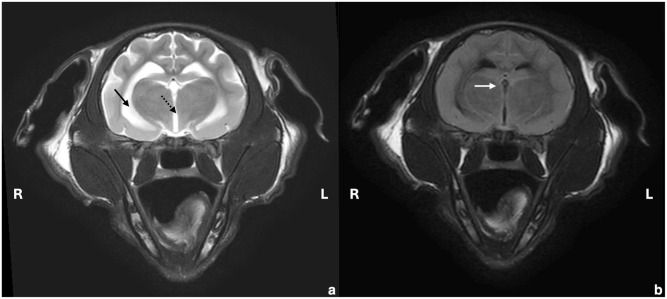

Case summary: A 6-month-old male British Longhair cat presented with acute neurological signs, ocular changes, massive ascites and laboratory parameters consistent with feline infectious peritonitis (FIP). Systemic and neurological signs fully resolved with initial treatment (GS-441524; BOVA UK [15 mg/kg PO q24h for 42 days], levetiracetam [20 mg/kg q8h] and prednisolone [1 mg/kg q24h until day 21]). Lethargy and fever reappeared 17 days after treatment. Four days later, severe multifocal neurological signs re-emerged. High-field MRI revealed multifocal intra-axial and intramedullary lesions in the brainstem and cervical spinal cord, severe meningitis and generalised mild ventriculomegaly. Feline coronavirus (FCoV) RNA was detected in the cerebrospinal fluid by reverse transcription quantitative PCR (RT-qPCR). Abdominal effusion was absent. Serum alpha-1-acid glycoprotein (AGP) was again elevated. FIP re-emergence was suspected, and antiviral treatment was resumed. After 1 day of GS-441524 treatment (15 mg/kg PO q24h), severe hypoventilation developed, requiring intubation and mechanical ventilation for 1.5 days. Treatment was switched to remdesivir (16.7 mg/kg IV q24h, Veklury; Gilead) for 4 days. Oral GS-441524 was then reintroduced (10 mg/kg q12h) and continued until day 84. Treatment resulted in partial recovery with moderate ataxia and reduced left-sided menace response remaining 181 days after starting the second treatment.

病例总结:一只6个月大的雄性英国长毛猫出现急性神经系统症状,眼部改变,大量腹水和实验室参数符合猫感染性腹膜炎(FIP)。初始治疗(GS-441524; BOVA UK [15 mg/kg PO q24h,连用42天]、左乙乙坦[20 mg/kg q8h]和强的松龙[1 mg/kg q24h,连用21天])后,全身和神经系统症状完全缓解。治疗后第17天再次出现嗜睡和发热。四天后,严重的多灶性神经症状再次出现。高场MRI显示脑干和颈脊髓多灶轴内和髓内病变,严重脑膜炎和广泛性轻度脑室肿大。采用逆转录定量PCR (RT-qPCR)方法检测脑脊液中猫冠状病毒(FCoV) RNA。腹部未见积液。血清α -1-酸性糖蛋白(AGP)再次升高。怀疑FIP再次出现,恢复抗病毒治疗。GS-441524治疗1天后(15mg /kg PO q24h)出现严重低通气,需要插管和机械通气1.5天。治疗转为瑞德西韦(16.7 mg/kg IV q24h, Veklury; Gilead),持续4天。然后重新引入口服GS-441524 (10 mg/kg q12h)并持续到第84天。第二次治疗后181天,患者部分恢复,伴有中度共济失调,左侧威胁反应减少。相关性和新信息:这个病例说明了诊断和治疗再出现的fip相关神经症状的复杂性。AGP监测为早期发现复发提供了一种有希望的非侵入性方法。通过适应短期和长期抗病毒治疗并提供重症监护,可以为患有严重复发的fip相关神经症状的猫获得良好的长期预后。